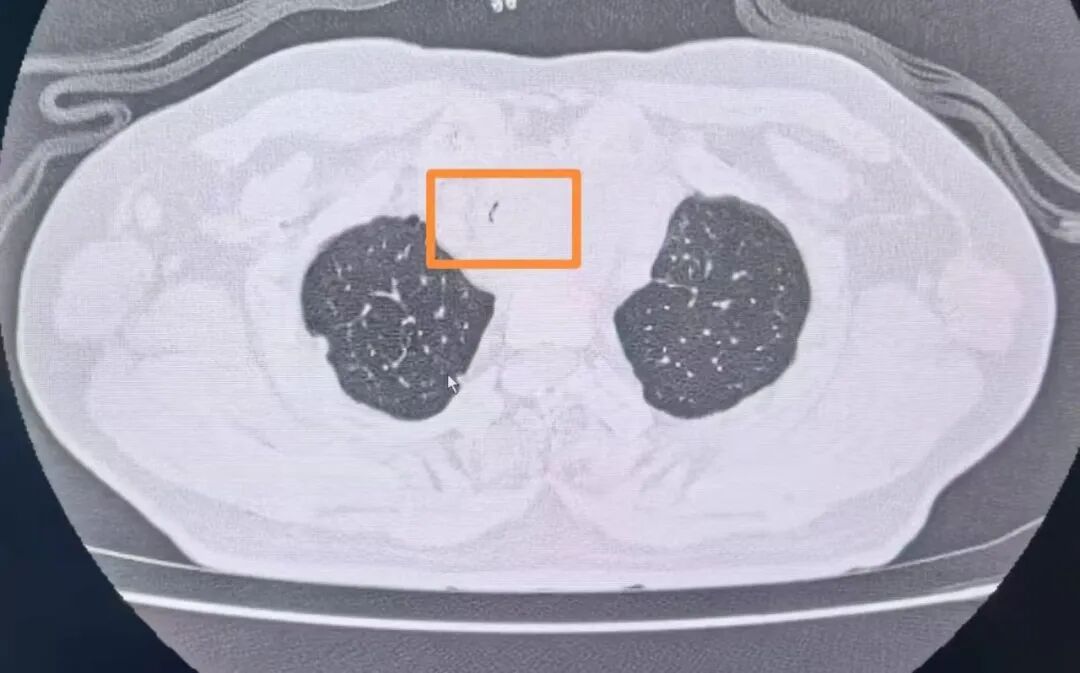

經復查胸部CT發現患者氣管已經出現明顯狹窄,內徑最窄處直徑不到2mm(正常成年男性氣管內徑為18-22mm),呈“一線天”樣改變,整個氣管僅靠一條細微的縫隙維持著少量的通氣,意味著病人隨時有發生窒息的危險。甲乳外科立即組織開展了多學科討論。經過對病情的充分分析,呼吸與危重癥醫學科副主任陳暉建議緊急行氣管內支架置入術解除大氣道梗阻。